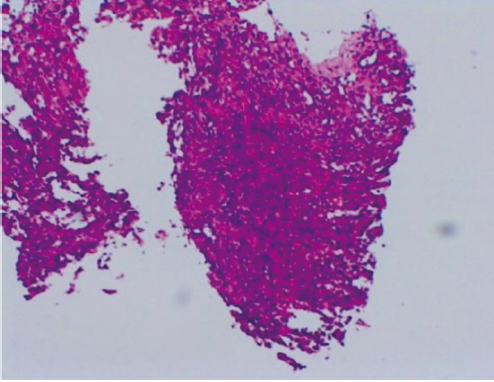

原发性心脏血管肉瘤是一种来源于血管内皮的恶性肿瘤,极为罕见且预后极差,病理诊断特异性及敏感性较高的标志物是CD31和CD34,手术不能根治性切除,姑息放疗、系统化疗和抗血管生成靶向治疗可延长患者生存期。现报道1例心脏原发血管肉瘤患者的诊疗经过,并就相关文献进行复习,以提高对该类疾病的认识。